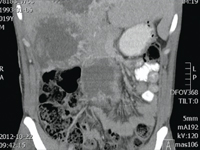

Krwawienie z przerzutu do wątroby u pacjenta z nowotworem jądra

Life threatening bleeding from metastatic testicular cancer in the liver

SurgeryMalignant tumors of the testicle are rare cancers - they account for only 1.5% of all malignancies malignant neoplasms, however, they are the most common solid tumor in 25-40 year old men. They constitute a diverse histologically a group of diseases. Most are characterized by high malignancy and an aggressive clinical course clinical course, and are usually sensitive to chemotherapy and radiotherapy.